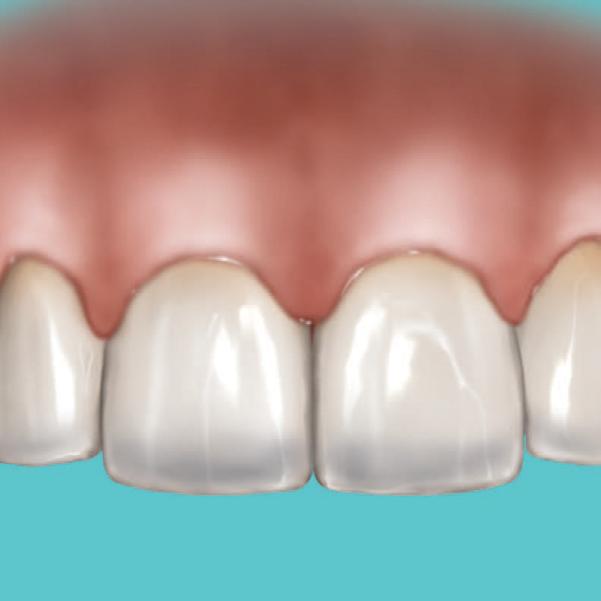

A significant number of people are unhappy with their smile, which has a considerable psychosocial impact. Although many seek cosmetic dental treatment, costs, fear and duration of total treatment are often barriers to the patients. Nevertheless, many could benefit from small and subtle changes to their teeth. With simple direct and freehand techniques, quick but significant results can be obtained that ultimately greatly improve the overall smile aesthetics.

Black triangles and diastemas can cause entrapment of the food and accumulation of bacteria, which leads to gingivitis and ultimately periodontitis. By eliminating the black triangles and diastemas with composite bonding, the dentist not only improves the aesthetics, but also protects the long-term health of the periodontal tissues.

Worn canine cusp restoration is of special functional importance. Creating functional canine guidance with a minimally invasive composite addition to the canine cusp will protect the posterior teeth during lateral movements of the jaw. Incisal wear restorations return the youthful appearance to the smile and prevent further loss of enamel and exposure of the dentinee.